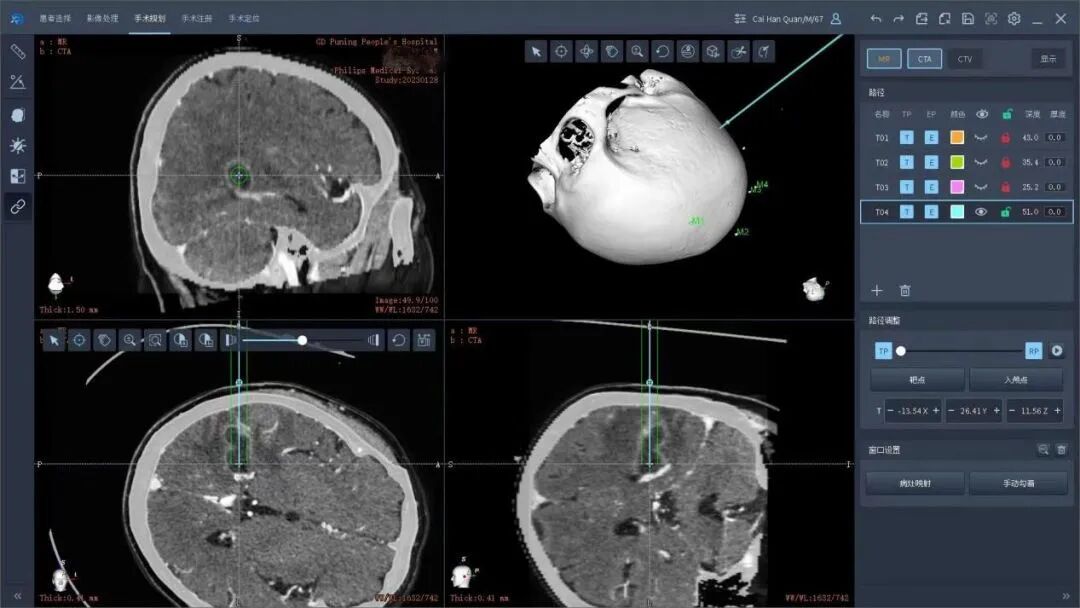

术前,谢树浩医师在患者头部贴上特制的标记后陪同前往CT室行头颅CT检查,在机器人手术计划系统上融合了患者的磁共振、CT等影像检查,避开了重要脑回、血管等重要结构,选择最佳的精准穿刺路径。在黄雪钦副院长指导下,王晓东主任医师治疗团队为陈老伯行机器人手术治疗。手术从机器人的注册、消毒、钻孔、置管一气呵成,置入引流管后,引流管内引流出大约6ml乳白色的脓液,明确了不是恶性肿瘤是脑脓肿的诊断,而且做到了精准无误的脓肿引流。术后陈阿伯清醒后拔除气管插管安返病房,复查头颅CT和mr显示脓肿清除满意。后期根据脓肿的细菌学检查进行下一步规范的抗感染治疗。

术前CT和MR多模态影像融合,设计最佳穿刺路径